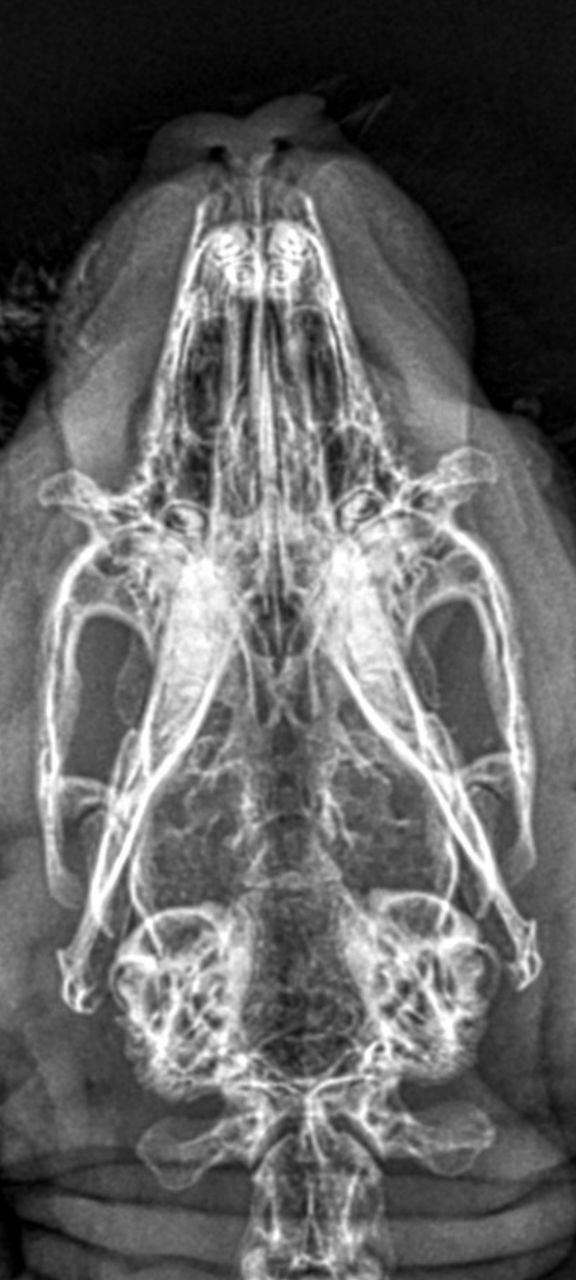

Am wichtigsten bei der Röntgenuntersuchung ist die dorsoventrale Aufnahme, d. h. das Kaninchen sitzt bzw. liegt gerade auf dem Bauch und der Schädel wird "von oben nach unten" geröngt. Auf die Weise können beide Mittel- und Innenohren nicht nur separat, sondern auch im Seitenvergleich beurteilt werden.

Wichtig ist eine absolut gerade Lagerung, da verkippte Aufnahmen Asymmetrien vortäuschen können. Hierfür hat es sich bewährt, das Kaninchen auf den Röntgentisch zu setzen, anschließend eine Mullbinde o. ä. über seinen Kopf zu spannen und den Kopf damit nach unten zu drücken, sodass das Kinn zwischen den Vorderbeinen auf dem Tisch zu liegen kommt. Die meisten Kaninchen tolerieren diese Lagerung völlig problemlos.

Mithilfe der Aufnahme kann insbesondere festgestellt werden, ob die normalerweise gut belüfteten Bullae tympanicae (Paukenhöhlenblasen) mit Sekret gefüllt, ihre Wände entzündlich verdickt oder Knochenauflösungen vorhanden sind.

Die Röntgendiagnostik liefert einen ersten Anhaltspunkt dafür, ob eine Oittis media / interna vorliegt. Eine Narkose ist hierfür nicht nötig und v. a. bei bereits geschwächten Tieren nicht zu empfehlen.

Gerade im Anfangsstadium einer Infektion ist es allerdings möglich, dass Veränderungen auf Röntgenbildern noch nicht sichtbar sind. Selbst bei Kaninchen, die bereits hochgradige neurologische Symptome zeigen, können die Mittelohren röntgenologisch noch unauffällig wirken - während sie im CT bereits deutlich sichtbar mit Sekret gefüllt sind.